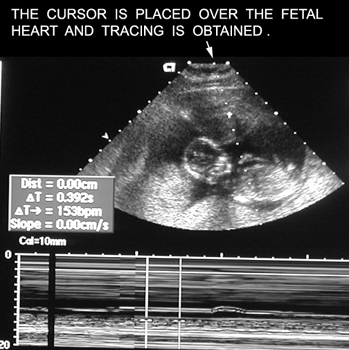

What is the normal fetal heart rate Answer

Doppler Fetal heart. Identify heart, descending aorta, carotid artery. Answer

Heart trace